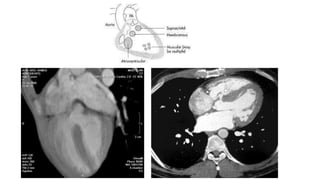

COARCTATION OF AORTA

• Radiographic features:

• Aortic figure 3

• Reverse figure 3 of Barium

filled esophagus

• Inferior rib notching (3rd to 8th,

>8 yrs, dt dilated intercostal

arteries)

• LV hypertrophy

figure 3 sign

COA

Aortic Caliber change local narrowing turbulent flow

3 figure sign due to pre and post dilatation, reverse 3 sign , dilatation of arch